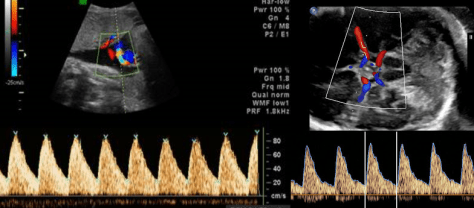

При скануванні ретельно оцінюються всі органі та системи: головний мозок, спинний мозок, обличчя, кістки, легені, діафрагма, серце, нирки, сечовий міхур, шлунок, кишечник, стінку живота, щоб діагностувати або виключити вроджені вади органів. Дослідження проводиться за допомогою кольорового та спектрального доплера, включно з ехокардіографією плода (УЗД серця плода).

Для оцінки внутрішньоутробного стану плода, характеру та причин затримки розвитку плода, наявності гіпоксичних змін проводиться додаткове дослідження (доплерографія). Всі показники доплерографічного дослідження порівнюються в графічних таблицях та оцінюються відповідно гестаційному віку.

Біофізичний профіль плода (БПП) + доплерографічне дослідження матково-плацентарного та плодово-плацентарного кровопливу:

Дослідження проводиться за показанням, у вагітних високого ризику: оцінюється сума балів окремих біофізичних параметрів (дихальні рухи плода, тонус плода, рухова активність плода, об’єм навколоплодових вод). Додатково проводиться доплерографія кровоплину в пуповині і середній мозковій артерії плода, в маткових артеріях.